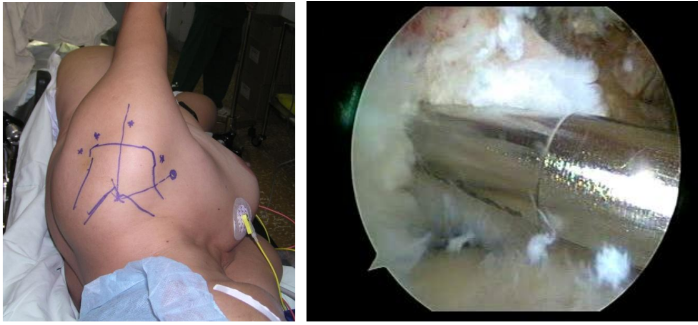

- Xác định các mốc giải phẫu và đường vào khớp vai (có 5 đường vào cơ bản tùy tổn thương mà lựa chọn vị trí đường vào thích hợp- hình dưới).

Hình minh họa: nội soi khớp vai trái tư thế nằm (hình bên trái) và hình ảnh cắt lấy tổn thương sụn bên trong (hình bên phải).